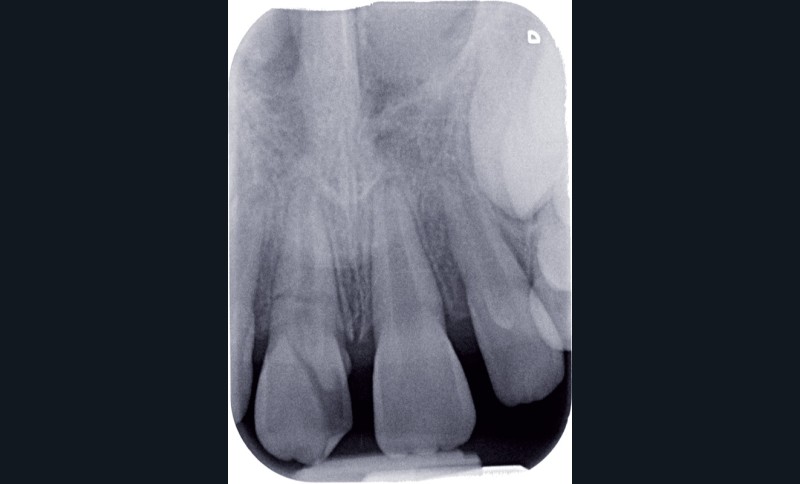

a à d Jeune patiente âgée de 8 ans, adressée suite à un traumatisme survenu 3 semaines auparavant, pour l’extraction de sa 21. La vue clinique montre un saignement ligamentaire, une mobilité coronaire et une fracture coronaire amélodentinaire longitudinale partant de l’angle mésial et se poursuivant en direction radiculaire sous-gingivale (a). Un test de vitalité positif indique que la dent est vitale, la radiographie permet de poser le diagnostic de fracture coronoradiculaire, et d’objectiver l’immaturité radiculaire (stade 8 de Nolla) (b). Une contention est mise en place et la plaie dentinaire coronaire est scellée au mieux par collage afin de limiter le risque d’une complication infectieuse (c). A 15 jours la dent est vivante et aucune complication n’est apparue (d). La patiente est revue après 3 mois pour déposer la contention, le test de vitalité est positif, et la radiographie de contrôle montre une apexogenèse en cours (e). Cependant la gencive s’est invaginée dans le trait de fracture (f). La zone est débridée sous microscope (g) puis scellée et reconstituée à l’aide d’un adhésif SAM et d’un composite fluide (h). Le contrôle radiographique à 6 mois est satisfaisant (i). Ce cas clinique illustre le fort potentiel des pulpes jeunes et du ligament alvéolodentaire à résister aux agressions et à assurer les fonctions dentinogénétiques et l’édification radiculaire.